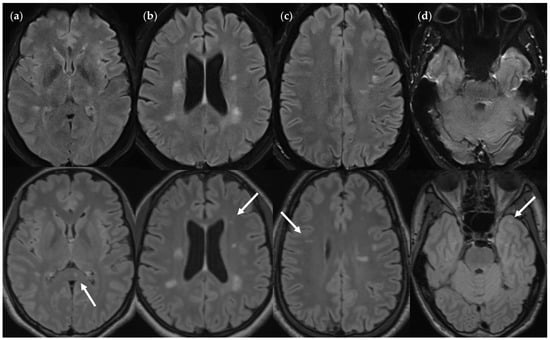

3.2.1. FLAIRUF Compared with FLAIR3Da

3.2.3. Dependence on Size and Location within FLAIRUF

3.3. Image Quality

4.3. Limitations of the FLAIRUF Images

4.4. Considerations on Ratings for Lesion Conspicuity in FLAIRUF

4.5. Outcomes Correlated with Technical Features